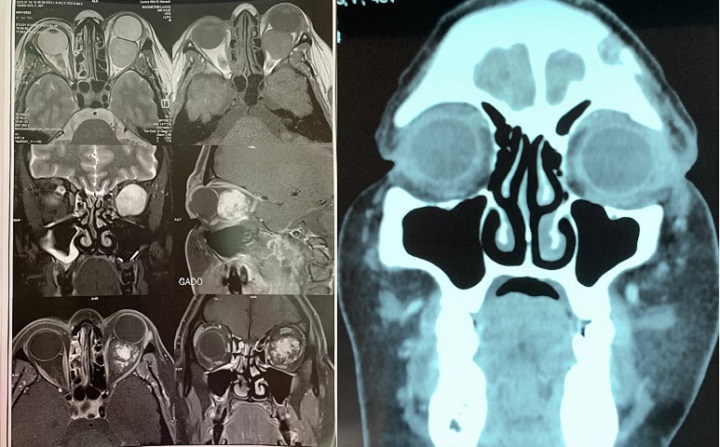

نجاح طبي في صفاقس: إستئصال ورم بالعين لمريضة عمرها 45 سنة

نجح الفريق الطبي المختص في جراحة الوجه والفكين وجراحة الاعصاب بالمستشفى الجامعي الحبيب بورقيبة بصفاقس، في استئصال ورم بالعين لمريضة عمرها 45 سنة.

وتميز هذا النجاح في دقة العملية الجراحية حيث تمت المحافظة على وظيفة النظر للمريضة وتفادي الاضرار بعصب العين الذي كان قريبا جدا من الورم الكبير الحجم.